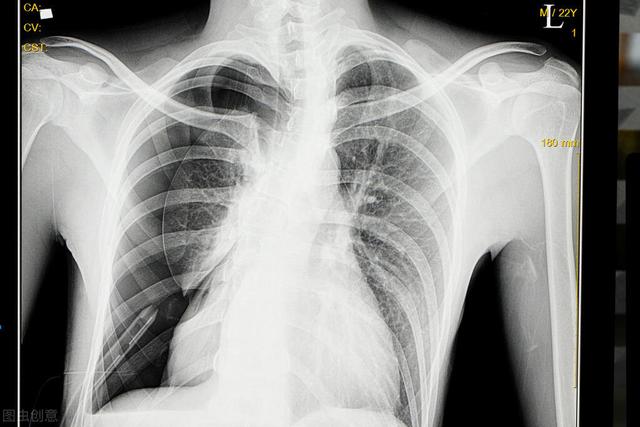

自然気胸の最も一般的な誘因は、激しい咳、労作、激しい運動などである。通常、胸痛を伴い、症状の重さはガスの量によって異なる。気胸の数が多いと、明らかな呼吸困難、あるいは呼吸不全を引き起こすことがあり、診断は通常、胸腔内のガスを確認できる胸部X線検査で確定される。

気胸が疑われる場合、主な検査は画像診断である。胸部X線と胸部CT.通常、気胸の存在を確認するには胸部X線検査で十分であり、患者によっては胸部CT検査が行われることもある。

胸のつかえや息切れに咳の症状が伴う場合は、なおさら呼吸器疾患を疑う必要があります。 肺や気管の病気をまず除外し、呼吸器内科で医師の指示を仰ぐようにしましょう。胸部レントゲン写真や胸部CTでさらに診断を明確にします。